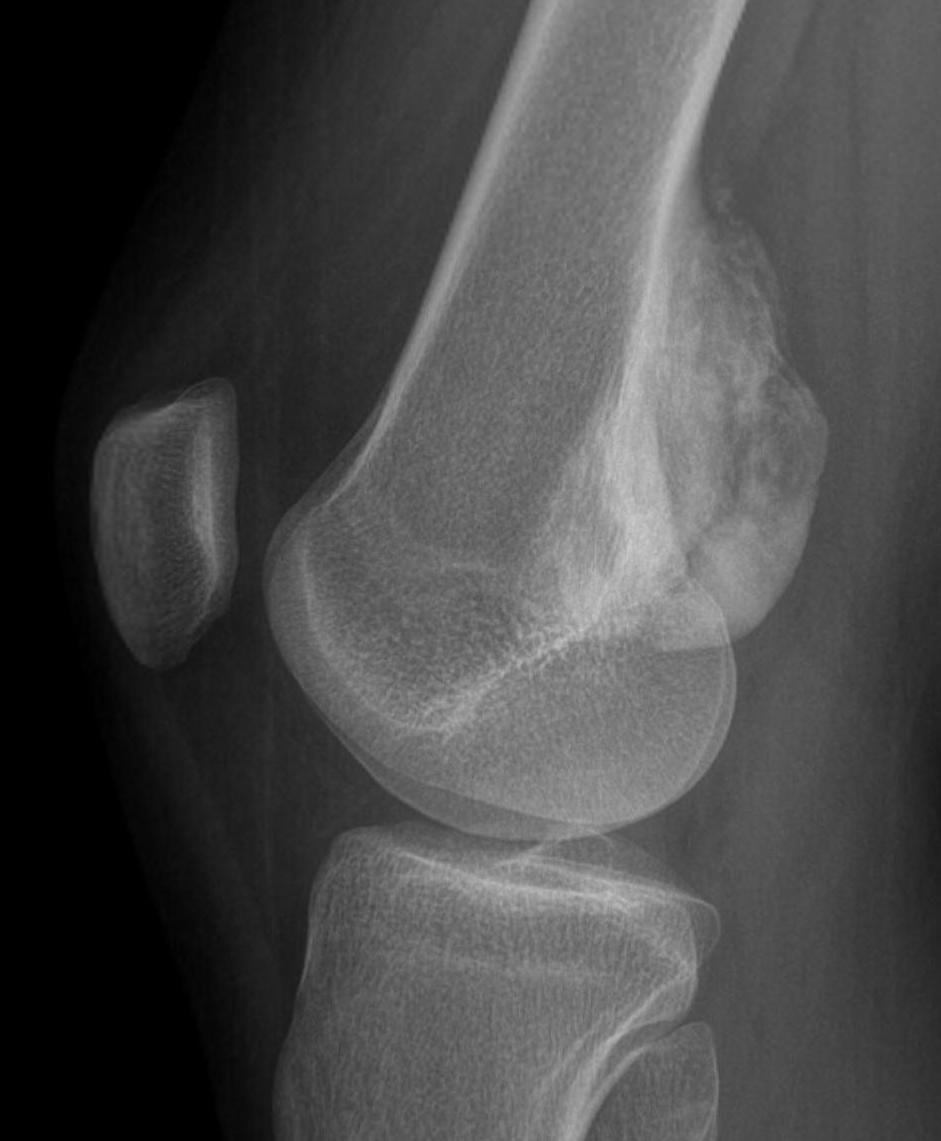

X-ray

May look like osteochondroma

- large lobulated broad-based lesion

- mature bone arising from cortex

- underlying cortex may be thickened

- 25% invade periosteum

"String Sign"

- wraps around bone with intervening periosteum

- well-defined radiolucent line between lesion & cortex

Parosteal osteosarcoma distal femur

Parosteal Osteosarcoma proximal tibia